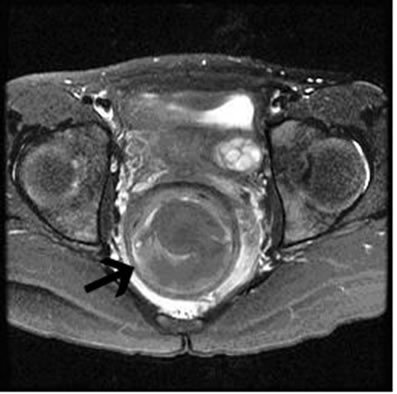

Initial imaging with a technetium scan was negative for heterotopic gastric mucosa that would be consistent with a Meckel diverticulum. Esophagogastroduodenoscopy and colonoscopy revealed a normal appearing stomach and duodenum with dark blood throughout the colon, but no source of active bleeding. Computed tomography (CT) of the patient’s abdomen and pelvis showed a 5.8x5.4x6.0cm heterogeneous fluid collection posterior to the anal canal and displacing the lumen anteriorly (Figure 1). A pelvic ultrasound also showed the mass, but did not provide any additional information. A barium enema confirmed the mass which was displacing the rectum anteriorly, but failed to show any communication between the two structures. Magnetic resonance imaging (MRI) for better visualization revealed a well-circumscribed, low-attenuating rim around the hematoma (Figures 2(a) and 2(b)), which was felt to represent a component of the rectal wall. After reviewing the patient’s history and clinical findings, it was felt that the most likely diagnosis was that of a rectal duplication cyst, and

Figure 2. T2 transverse (a) and midsagittal (b) MRI images showing the fluid-filled cyst (arrow) surrounded by a well-circumscribed, low-attenuating muscular layer.